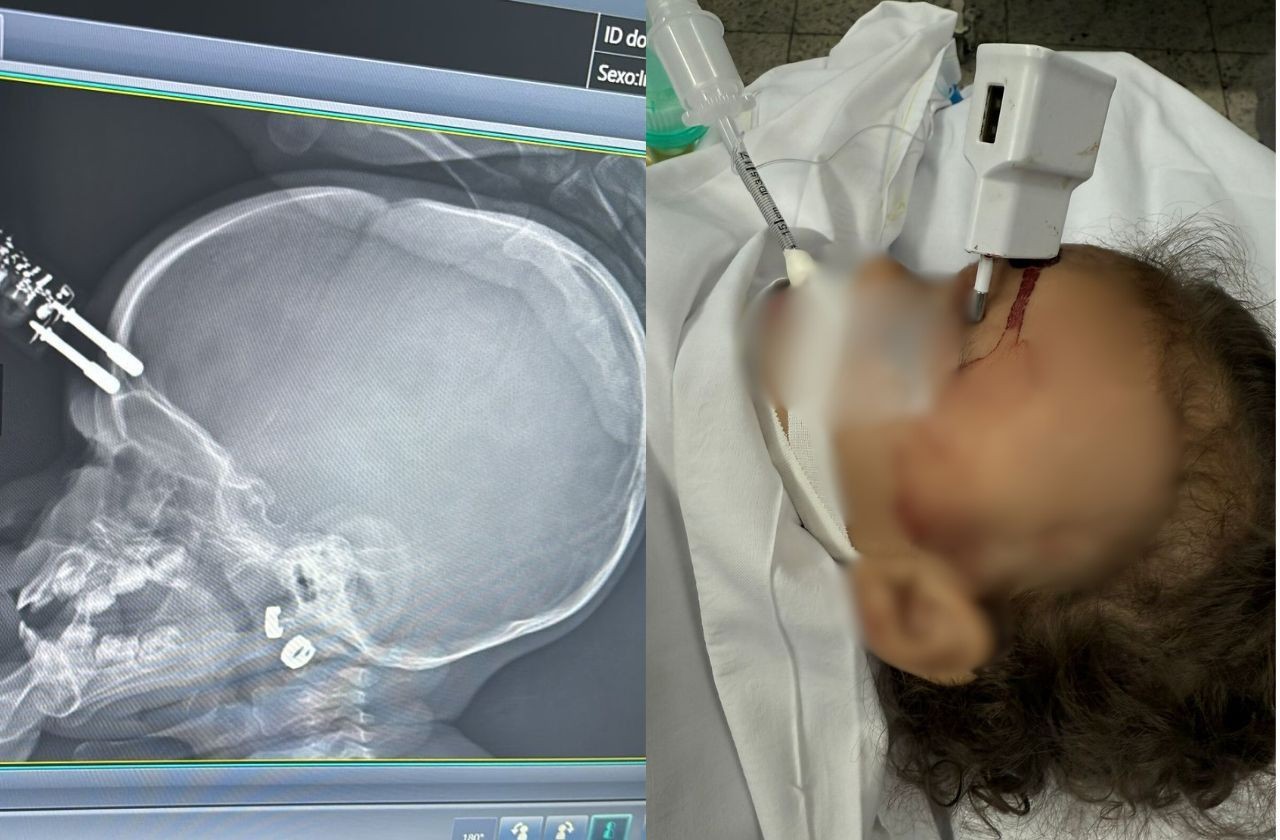

A hipótese mais provável para o acidente é que a menina estivesse segurando o carregador no momento da queda. O objeto, com suas pontas metálicas, perfurou a região frontal da cabeça da criança, perigosamente próxima à área ocular. Dr. Bruno Castro enfatizou a gravidade potencial do incidente, mencionando que um impacto direto no olho poderia ter resultado em perda permanente da visão, destacando a sorte na localização da lesão.

Imediatamente após o incidente, a menina foi submetida a uma cirurgia de emergência no Complexo de Saúde São João de Deus. Durante o procedimento, a equipe médica conseguiu remover o carregador com sucesso e realizou a reconstrução da área afetada. A agilidade no atendimento médico foi fundamental para evitar complicações severas, como hemorragias extensas, infecções e o risco de meningite, uma inflamação grave das membranas que envolvem o cérebro e a medula espinhal.